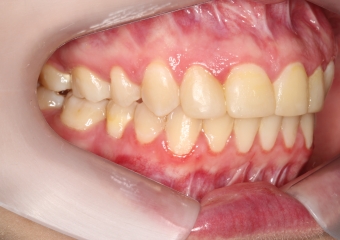

Oclusão após a cirurgia 2019